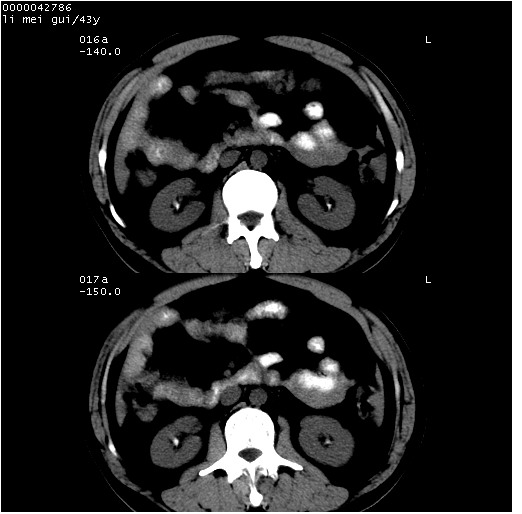

| 患者,男,43岁。突发腹痛2小时,面色苍白,难以平卧。自述近期无明确外伤史,为摩托车驾驶员。 腹部b超检查:脾脏中上极回声异常,肿瘤待排。 临床诊断:腹痛原因待查。 上中腹部ct轴位平扫+增强扫描(层厚10mm,螺距1.0,重建间隔10mm),图像如下: ![]() ![]() ![]() ![]() ![]() ![]() ![]() ![]() ![]() ![]() ![]() ![]() ![]() ![]() ![]() ![]() ![]() ![]() ![]() ![]() ![]() ![]() ![]() ![]() ![]() ![]() ![]() ![]() ![]() ![]() ![]() ![]() ![]() ![]() ![]() zrs发言:支持脾破裂 wwp发言:支持脾破裂并腹水。 xulianj发言:脾脏肿瘤破裂可能性大 zsl6918发言:不像肿瘤出血,考虑还是与外伤后引起的慢性出血有关 zzyy发言:平扫见肝周及脾周积液,脾内密度不均。脾内肿瘤较少见。还是外伤性脾破裂。 沈丘东方医院发言:脾门区一个不均匀强化病灶与其周液体相连多考虑脾占位破裂出血 yixianman001011发言:脾破裂并腹水是可以肯定的,具体原因多以肿瘤性破裂出血,脾脏淋巴瘤可能性大. 结果: 术后,经详细询问患者,其仔细回忆:一月前骑摩托时左侧腰部与别人有“轻微”触碰,因责任在自已,当时又无明显不适,未引起注意。 临床术后诊断:脾破裂并失血性休克(1.外伤性迟发性脾破裂。2.脾脏肿瘤破裂?) 术后标本病检:脾破裂并出血,未见明显肿瘤成份。 原贴地址:http://www.radinet.com.cn/forum_view.asp?forum_id=4&view_id=34070 |